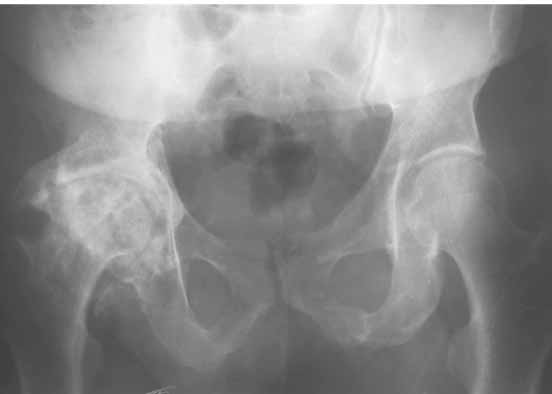

Для ответа на Ваши вопросы нужна, как минимум, обзорная

рентгенограмма таза в прямой проекции - многое станет ясно без слов.

Обзорная рентгенограмма таза просто необходима. Удивительно, почему она не сделана сразу же после установки протеза.

После ее получения можно будет продемонстрировать причины проблемы.

ошибочно заданным углом антеверсии и, скорее всего, с избыточным удлинением - именно это мы и увидим на передне-задней рентгенограмме(!) таза.

> Обзорная рентгенограмма таза просто необходима. Удивительно, почему

> она не сделана сразу же после установки протеза.

> После ее получения можно будет продемонстрировать причины проблемы.

Да, это разумно.

Причем рентгенография должна быть сделана с правильной укладкой пациента, а именно - голени должны свешиваться с рентгеновского стола и край стола проходить на уровне коленных суставов.

Тогда можно будет точно установить угол антеверсии.

1. AP X ray of the Pelvis is a must. It will likely show that right hip/ femur is longer than left. Even based on Rt Hip AP X Ray it is my impression.